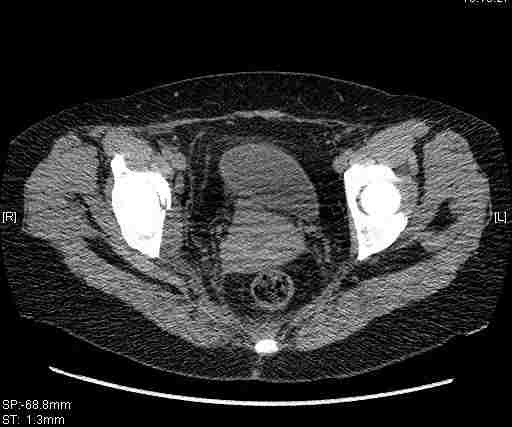

[Ortho] [1/2] Re: Т-образный перелом вертлужной впадины

Удалось сегодня вывести пациентку в соседнюю больницу, где есть кт.

Срезы сделаны  только горизонтальные.